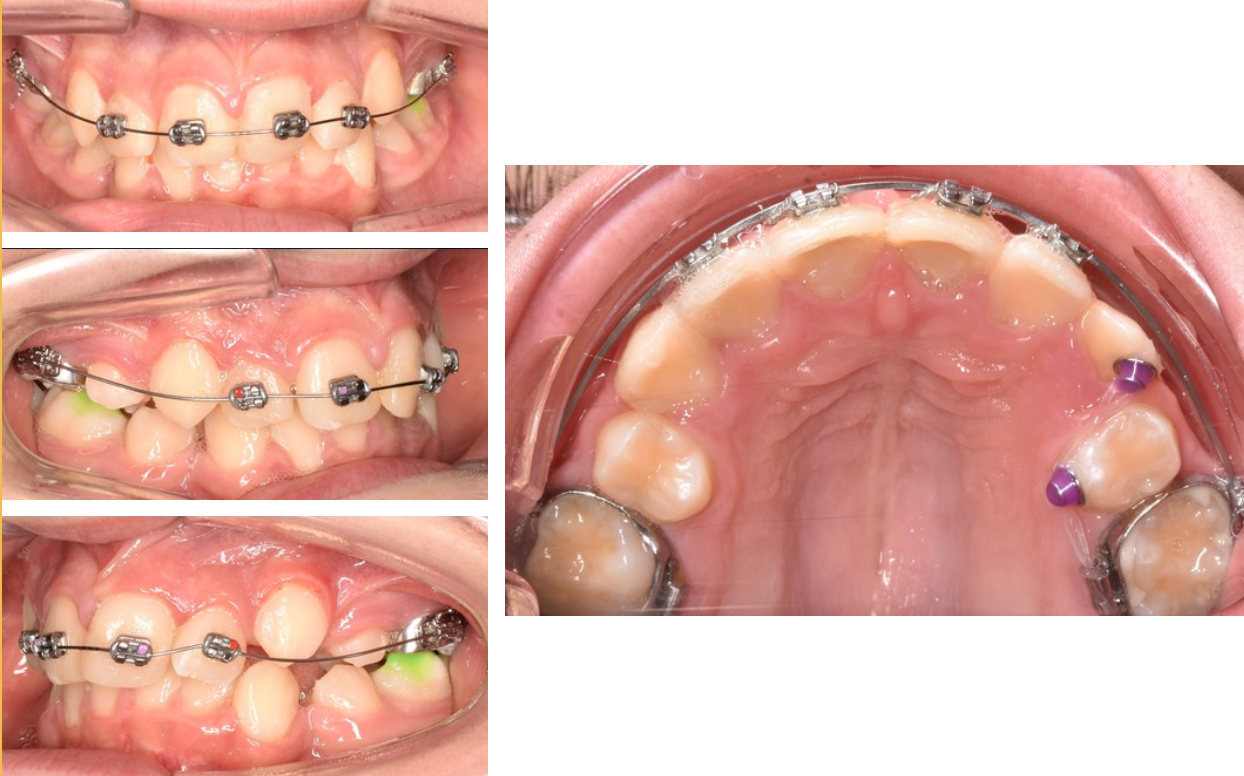

În general pacienții solicită un tratament ortodontic în momentul în care sunt nemulțumiți de aspectul zâmbetului lor, cel mai frecvent observă dinții nealiniați, înghesuiți (Fig. 6.1.1). Există însă și alte semne care ar trebui să îi trimită pe pacienți la un consult ortodontic: abraziunile dentare (dinții tociți) – un semn că sistemul masticator suferă, durerile articulare, musculare, de cap – pot apărea ca urmare a unei mușcături incorecte. Este bine ca pacienții să facă regulat controale la medicul dentist, care poate observa anumite probleme și îndruma spre un consult ortodontic. Acest lucru este valabil și în cazul copiilor, deoarece anomaliile dentare și mai ales cele scheletale sunt mai ușor de influențat și corectat la vârste fragede decât după încetarea creșterii.